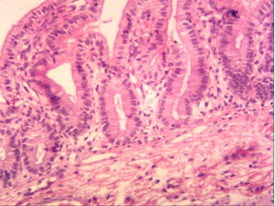

下面是實(shí)拍的圖片: